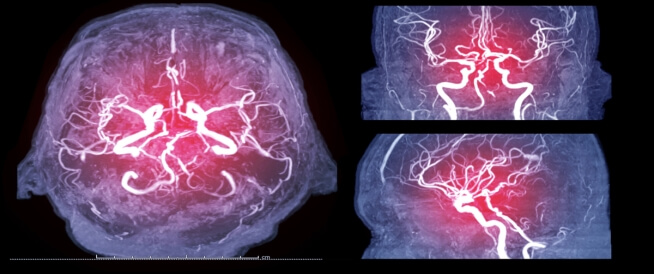

يتم إجراء قسطرة الدماغ أو ما يعرف بتصوير الأوعية الدماغية أو التصوير داخل الأوعية الدموية بالطرح الرقمي للكشف عن مشكلات عدة تصيب الدماغ ليتم لاحقًا علاجها، ويجب على المريض أن يتلزم بمجموعة من التعليمات قبل وبعد العملية. المزيد عن قسطرة الدماغ في المقال:

تتم عملية قسطرة الدماغ بإدخال قثطار وهو أنبوب طويل ورفيع ومرن في أحد شرايين الذراع أو الساق، وباستخدام أنبوب القسطرة يحقن الطبيب صبغة طبية داخل الأوعية الدموية وصولًا للدماغ، ولاحقًا تظهر صور الأشعة السينية أي اضطرابات في الأوعية الدموية داخل الدماغ.

تجرى قسطرة الدماغ عادةً بعد أحد الفحوصات الأولية التي تشير لوجود مشكلة، إذ تعد نتائج الصور الدماغية أكثر دقة وتستطيع الكشف عن وتشخيص السكتة الدماغية الحادة.